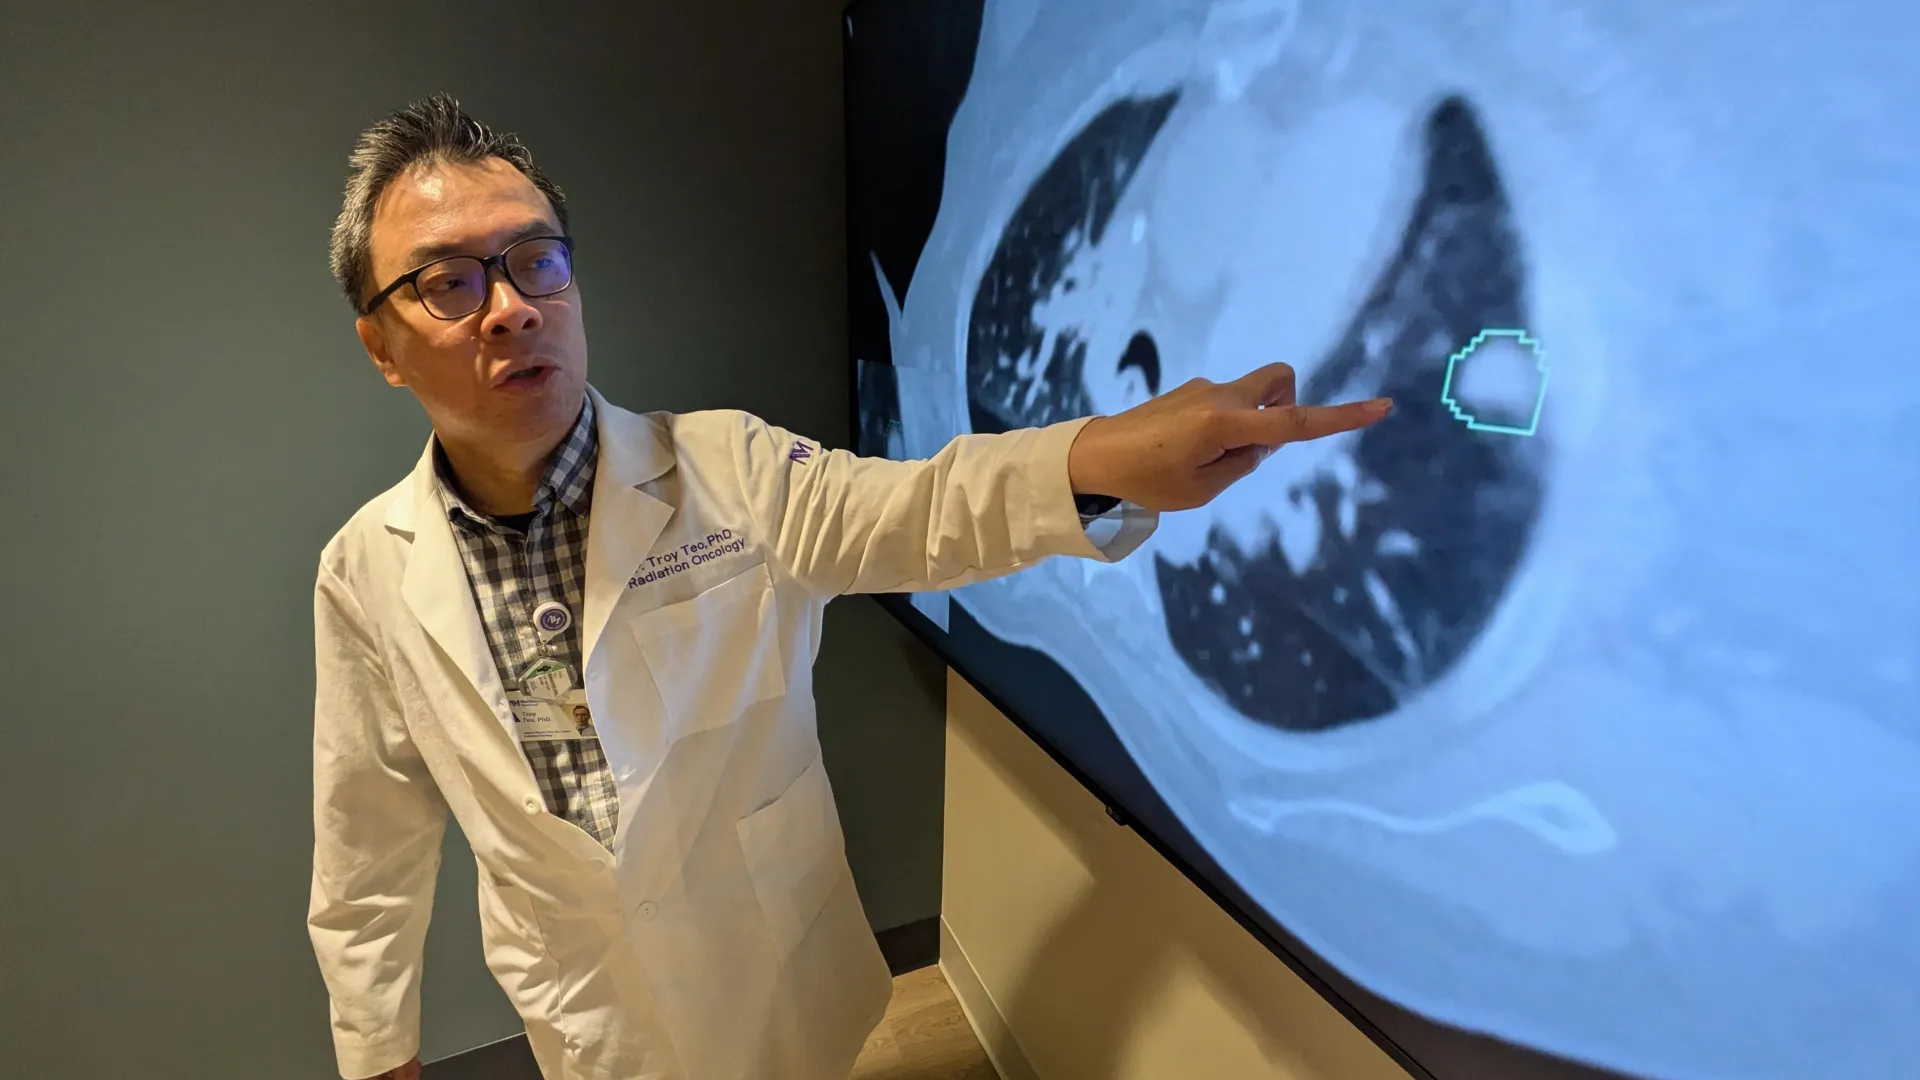

New research from UC Davis Comprehensive Cancer Center has uncovered an evolutionary change that may explain why certain immune cells in humans are less effective at fighting solid tumors compared to non-human primates. This insight could lead to more powerful cancer treatments. The study was published in Nature Communications. It…